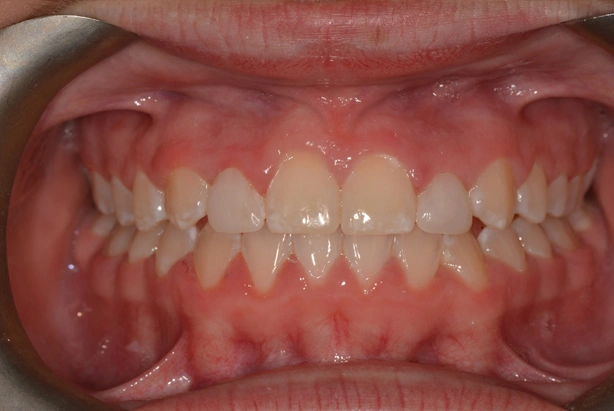

Peg Shaped Laterals

Diminutive lateral incisors are one of the most common problems we see. After careful assessment with patient, parent and referring dentist, it was decided to complete full fixed appliance treatment with space creation for composite buildups of the 12 and 22.

Alignment and occlusion were perfected and the patient referred back to dentist to approve of space distribution.

Appointments were coordinated so that all appliances were removed in the morning. Build-ups undertaken around lunch and final retainers issued by the end of the day.

A great result. With potential permanent indirect restorations after growth completed if needed.